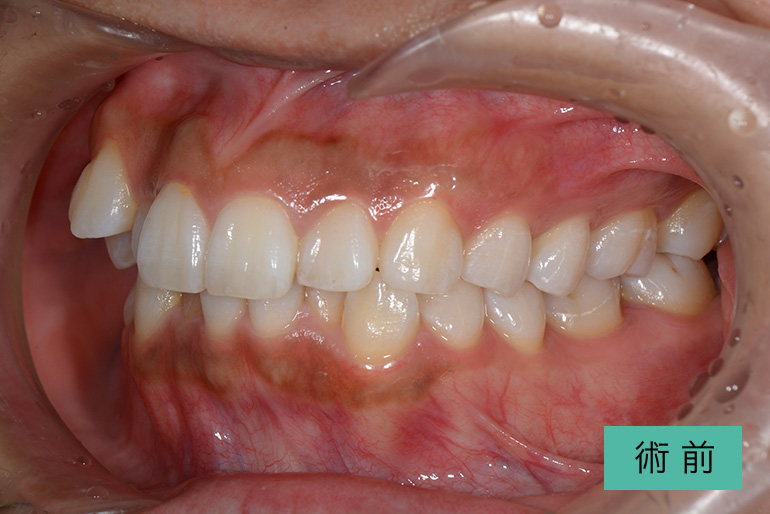

インビザライン②

| 治療内容 | 歯並びをキレイにしたい。 口腔内容積を狭くしないように、歯列を拡大し非抜歯で矯正をする。 |

|---|---|

| 治療期間・回数 | 約3年半、40回 |

| 費用(税込) | ¥880,000(マウスピース矯正) ※自由診療 |

| リスク・副作用 | 歯肉退縮、知覚過敏、後戻り |